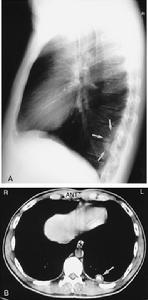

2.X線檢查胸片示兩肺多發性病變,早期多為非特異性間質浸潤,繼而出現浸潤性,結節性,甚或空洞性病灶,孤立性腫塊等,類似肺炎、結核、肺癌等,少數病人可因肉芽腫阻塞氣道形成肺不張。支氣管體層顯相示氣管或支氣管狹窄。上呼吸道X線顯示鼻竇黏膜增厚,甚至鼻及鼻竇骨質破壞。